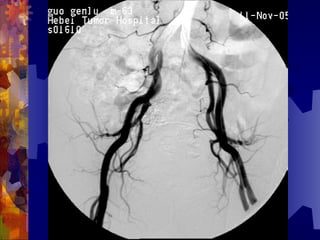

男, 86 岁

双下肢多普勒血流图未探及血管

动脉造影血管闭塞